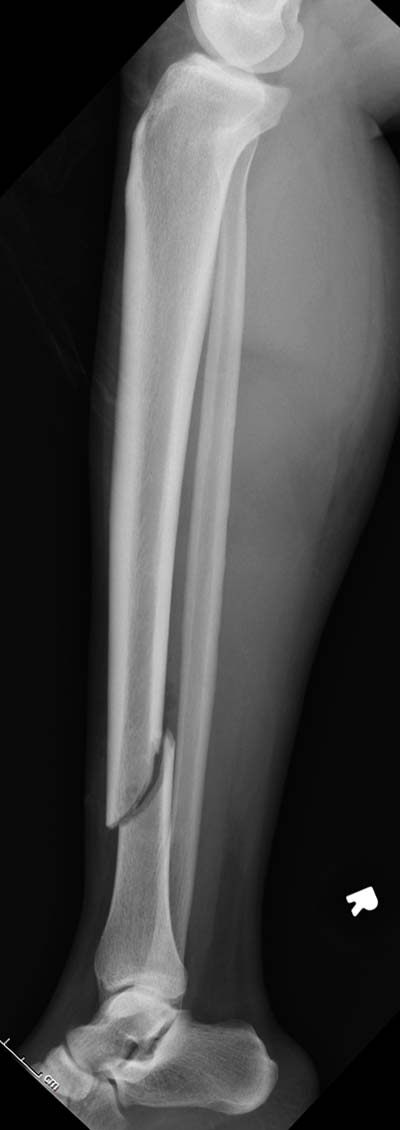

Разбор любого случая кому-то поможет лучше ориентироваться в решении вопросов, потому что в нашей работе встречаются разные связанные и несвязанные с мастерством хирурга ситуации. Возможно, отсутствие полного набора гвоздей повлияло на выбор короткого имплантата, имеется угловая и ротационная деформации. Независимо от локализации, стабильность создается, когда гвоздь проксимально не глубже 1.5 см (облегчает удаление) и дистально доходит до epiphyseal scar.

Кроме этого, имеет значение предварительная репозиция и риминг в центре канала. Интактная малоберцовая иногда затрудняет репозицию, но существуют разные приемы, нп. при застарелом можно применить дистракторы: стержневой или кольца Илизарова, а при свежих - перкутанно Weber clamp.

Мнение о том, что гвоздь сделает репозицию не всегда соответствует истине. Снимки показывают на неудачную попытку исправить направление гвоздя с помощью “поллеров”. Прием возможен только тогда, когда проход риминга в центре канала, иначе толкать гвоздь некуда.

Здесь несколько снимков изолированного перелома большеберцовой с интактной малоберцовой. Weber clamp, блокирующие спицы и риминг в центре канала отрепонировал перелом....